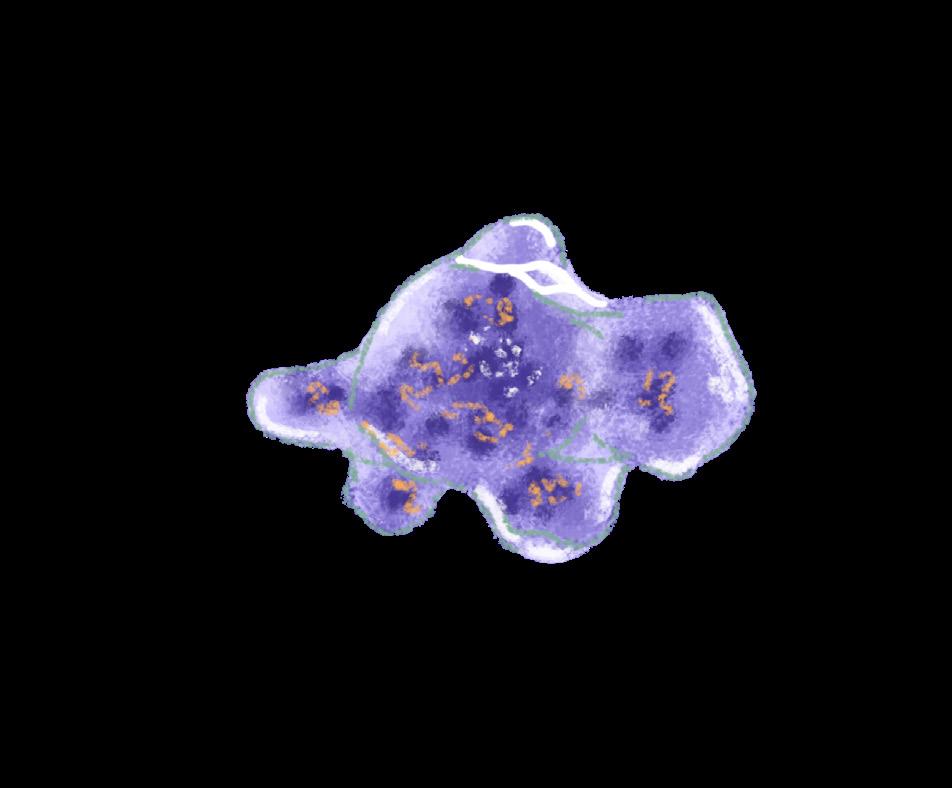

Naegleriafowleri, commonly referred to as the “brain-eating amoeba,” is an amphizoic amoeba that exists as both a freefloating organism and a parasite.1,2 Infection by N. fowleri is deadly in humans, exhibiting a fatality rate of 97%.3 As a free-living amoeba, N. fowleri can transition between three phenotypes depending on its environment: trophozoite, flagellate, and cyst. Under nutrient-rich conditions where N. fowleri can proliferate, it assumes a trophozoite form, which is reproductively active and infectious to humans. During this stage, it can cause primary amebic meningoencephalitis (PAM), a rapidly fatal infection of the central nervous system (CNS). Conversely, under nutrient-poor conditions, N. fowleri can temporarily transform into its flagellate form. Though this form is unfavourable for growth, it facilitates long-distance travel to search for nutrients.2,4 Finally, under environmental stress, such as the absence of water and lower temperatures, N fowleri switches into its metabolically inactive cyst form, which can withstand temperatures from 0°C to 65°C.4

The pathogenic mechanisms of N. fowleri infection consist of phagocytosis, secretion of proteases, phospholipases, and pore-forming proteins (PFPs). N. fowleri utilise structures resembling suction cups known as amoebastomes to consume neurons through contact-dependent phagocytosis, leading to the progressive destruction of brain tissue.7 The amoeba also prompts the release of PFPs, membrane-bound proteins that degrade the stability of the host cell membrane, causing cell death.9 Additionally, N. fowleri can cross the blood-brain barrier (BBB) by destroying the tight-junction proteins (TJPs) between host endothelial cells. This mechanism involves secreting cysteine protease that degrade TJPs and modify the cell’s cytoskeleton, breaking down the BBB.8 The amoeba also uses phospholipase enzymes to destroy neuronal myelin by degrading phosphatidylcholine, a major structural component of the myelin sheath.

The presence of trophozoites prompts macrophages and other immune cells to release cytotoxic molecules, resulting in necrosis of olfactory tissues.5,9 Further, N. fowleri has evolved to evade immune mechanisms and has become resistant to destruction by cytolytic immune processes.9 Microglia, the neuronal immune cells, activate immune signalling pathways in response to the amoeba for the secretion of cytokines. However, the proteases and signalling molecules secreted by N. fowleri can cause microglial lysis.9 As amoebal growth within the host progresses, a positive feedback loop of leukocytes and pro-inflammatory cytokines is initiated, resulting in uncontrollable CNS inflammation.9 This inflammation prevents the CNS from controlling the infection, leading to fatal haemorrhage and edema.9